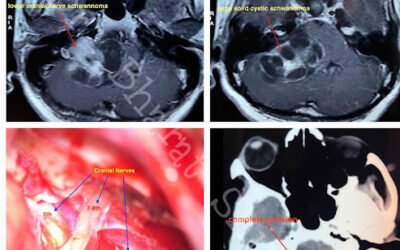

Lower Cranial Nerve Schwannoma

Which nerves are called as Lower cranial nerves: 1. 9th: Glossopharyngeal2. 10th: Vagus3. 11th: Spinal accessory nerve What is Schwannoma ?Nerves are covered with Schwann cells. Tumor arising from it is called as Schwannoma. Are these tumors...